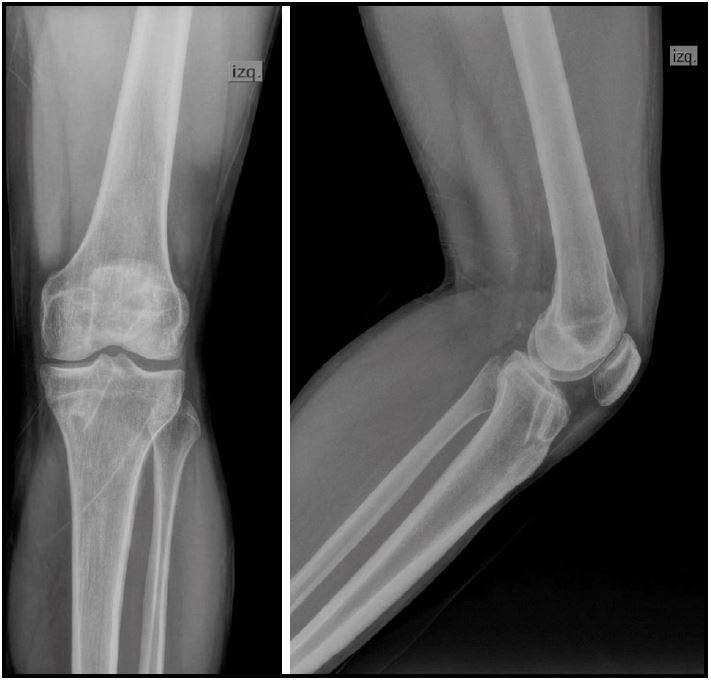

Al primer mes del postoperatorio, se realizaron radiografías de frente y de perfil de la rodilla para evaluación de la orientación de los túneles y posición de los elementos de fijación (Fig. 3).

Figura 3. Radiografías de frente y perfil para evaluar la posición de los túneles.